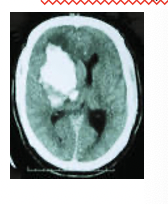

What is this

Intracerebral ahemorrhage